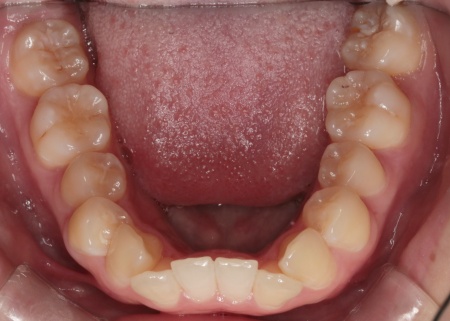

治療前

| 診断結果 | 拝見したところ、上下の歯はデコボコに生えている状態でした。 このままでは見た目が気になるだけでなく、磨き残しが起こりやすくなることで虫歯や歯周病などの発症リスクが高まります。 以上のことから、歯並びを改善する矯正治療が必要だと診断しました。 |